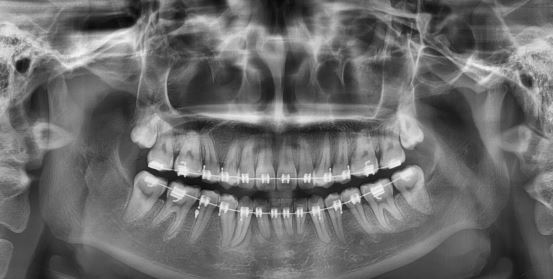

마무리단계

마무리 해도 될거 같다고 하시는데요. 윗니가 아랫니 덮는 정도가 적당한건지 궁금해요. 그리고 아래앞니 두개가 높이가 안맞는데 교정 가능한건가요??

교정마무리 하는데 앞니 교합이 이상합니다

지난8월 비발치교정을하고 얼마전 마무리하자고 하시더니 유지장치까지 달았습니다 그런데 앞니 교합이 안맞는것같아요 휴지를 물면 그냥 빠져나갈정도로 떠있습니다 이대로 장치를 땔까 겁나서요 교정중 저는 고무줄...

우측1,2번 조기접촉때문에 교합조정했는데 그 부분만 휑하니 교합이 들린느낌으로 좌우 교합 밸런스가 안맞아요 ㅜ

돌출입 비발치 교정 9개월차입니다. 3개월차 당기기시작하고 부터 교합이 전체가 계속 안맞음을 느꼈고 하악우측 1~3이 상악보다 덜 들어가서 아랫니가 상악우측 1, 2를 들어올려 들썩들썩하다가 지금으로부터 3주전 ...

블랙트라이앵글 당기기중에도 생기나요?

제가 알기로는 펴기하면서 겹쳐있던 부분이 펴지면서 공간이 생기고 잇몸이 재생되지 않는걸로 알고있는데 펴기가 끝날때까지 보이지 않다가 이번에 당기기 시작한지 두달정도 되는데 아랫니부분에 전부 블트가 갑자...

발치공간 닫히는 속도가 다릅니다.

교정한지 1년이 지났구요 발치를 하고 당기기 시작한지 약 6개월 정도 지났습니다. 현재 오른쪽 왼쪽 윗니 2개를 발치하였는데 오른쪽 발치한 공간은 거의다 매꿔졌는데 왼쪽은 아직도 구멍이 보일정도로 공간이 남아...

어금니가 후방으로 이동이 가능한가요

교정 진행중이며 1년8개월 되었습니다 상악발치공간 왼쪽 3mm 남았고 오른쪽은 5mm남았습니다 하악은 이미 닫혔고요 문제는 하악 어금니가 너무 앞으로 이동해서 음식물을 씹을려면 턱을 최대한 당겨서 씹어야 하는 ...

치아재교정 중입니다.. 꼭좀 봐주시고 답좀주세요 너무불편해요.

예전 2013년도에 치아첫교정을 시작했습니다. 첫 교정은 지금 하는 치과에서 하지않았고 다른치과에서 했습니다. 그런데 원래 턱불편한것도 없고 교합도 잘맞았었는데 처음 교정한곳에서 잘못하여 이렇게된거같습니다...

문의드립니다.

매복 송곳니 견인중입니다. 치아가 고른 상태로 시작했습니다. 1년정도 윗니를 공간을 만들어준후, 현재 11월부터 송곳니 견인중에 있습니다. 현재 앞니 바로 옆니 뒤에 송곳니가 위치해 있는데 움직이지 않아요. 타...

치아교정중 설소대수술

안녕하세요? 10살 여자아이 교정중입니다. 아랫턱이 윗니에 비해 더 많이 나오고 있는상황에서 교정 들어갔구요 윗니는 좁아서 송곳니가 나오지 못하고 막혀 있어서 윗니를 벌려 주면서 앞으로 나오게 해야 한다는 설...

미니 임플란트 질문 입니다

미니 임플란트 꼭 해야 하는 건 아니죠 잇몸 이 약해 철사 로만 교정 진행 을 해야 한다고 그래서요 발치 했어요

치아교정 비발치에서 발치로 변경 가능할까요?

안녕하세요, 2014년 12월 초부터 시작해서 지금까지 약 1년 6개월 정도 교정치료를 받고 있습니다. 상악의 경우, 견치 좌우 모두 영구치가 나오지 않고 비골쪽 안에 박혀있어서 대학 병원에 의뢰해서 교정 전에 모두 ...

교정진행중 마지막단계 부정교합으로 스크류장치설치를했어요ㅜㅜ

선생님안녕하세요~ 걱정이되서 전문의사선생님께 물어보고싶어 글을올려봅니다ㅜㅜ 교정한지이제 이년반다되가구요 거의 일년전에 돌출교정은다끝나고 부정교합때문에 고무줄을걸어야하는 상황인데 제가 타지로 이사...

조언 꼭 부탁드립니다

안녕하세요 저는 교정한지 2년 쫌 넘었구요 교정을 시작한이유는 심한 개방교합과 고르지 못한 치아 때문이였습니다 첫번째 치과에 갔을때 수술을 해야한다 하였고 두번째 치과에서는 수술까지는 필요없다고 하여서 ...

교정중에 과개교합이 왓어요 ㅠ

교정 마무리 단계인데, 과개교합이 왔어요.. 의사샘은 저보고 스크류를 하자고 하는데 사람들 보니깐 스크류 하다가 염증생겨서 다시 뺏다가 심는 사람들도 있고, 정말 심각한 경우는 신경이 손상됐는지 이가 시려하...

오늘 월치료 받고온 날인데 궁금한 점이 있어요

철사맨 선생님 안녕하세요!! 지난 달 내원 당시 턱관절 증상이 심해져 입을 다물 때 아래 위 어금니끼리 덜 닿이도록 하기위해 아랫쪽 양 어금니부분에 파란색으로된 어떤 물질을 붙이고 갈아서 높이를 맞췄다가 오늘...

교합 마무리 조언 부탁드려요~~~

안녕하세요 위아래 앞니는 이미 교정기도 거의다 뗀 상태고 어금니 쪽에만 교정기가 몇개 남아 있는데 교합 때문에 고민이 많아 매일 잠 못들고 있어서 선생님께 도움 요청 드립니다. ㅠㅠ 일단 첨부한 사진상으로 보...

철사맨 도와주세요 ㅠㅠ

교정 6년째하고있어요,,ㅠㅠ 위에는 끝나서 장치 다떘는데 (위에도 작년에땜) 아래가 문제에요,., 어금니쪽이(맨뒤쪽치아) 치아가 원래 기울어져있었는데 그쪽을 세우지않고 그냥 깍아서 씌워버렸꾸요 그옆에이빨은(...